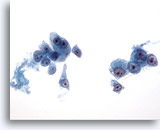

画像 2: 肝FNA – 良性肝細胞

反応性変化を来した良性肝細胞の集塊。細胞境界が明瞭な立方形の細胞が認められます。不透明な細胞質には空胞が認められるものもあれば、幾分顆粒状を呈するものもみられます。辺縁部は擦り切れた状態を呈しています。核はわずかに大小不同で、二核を有する細胞も認められます。小型の核小体がみられます。

40倍

画像 2

肝FNA – 良性肝細胞

反応性変化を来した良性肝細胞の集塊。細胞境界が明瞭な立方形の細胞が認められます。不透明な細胞質には空胞が認められるものもあれば、幾分顆粒状を呈するものもみられます。辺縁部は擦り切れた状態を呈しています。核はわずかに大小不同で、二核を有する細胞も認められます。小型の核小体がみられます。

40倍